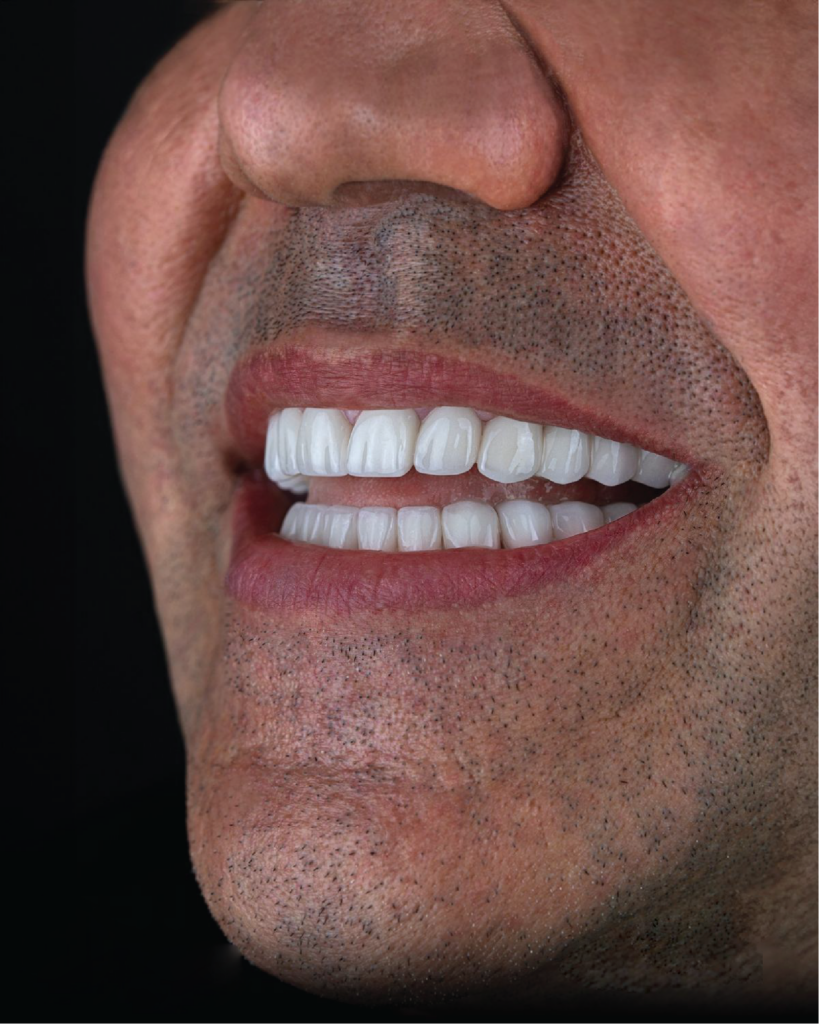

Gli impianti dentali All-on-4 / All-on-6 rappresentano una soluzione innovativa per chi soffre di una perdita multipla dei denti. A differenza delle protesi rimovibili tradizionali, offrono maggiore stabilità, comfort Q praticità.

La procedura prevede il fissaggio di una protesi fissa su radici dentali artificiali ancorate saldamente all’osso mascellare. Il risultato è una soluzione

affidabile, funzionale e duratura, ideale per ripristinare il sorriso e la qualità della vita.

La mancanza di denti, se non trattata, può causare problemi funzionali come difficoltà nella masticazione e riassorbimento dell’osso mascellare. Le tecniche All-on-4 e All-on-6 rappresentano una soluzione efficace sia per la perdita parziale che totale dei denti. Ancorando radici dentali artificiali in modo stabile all’osso e applicando protesi fisse dall’aspetto naturale, è possibile ripristinare estetica e funzionalità. Il numero di impianti necessari viene definito in base alla struttura ossea e al grado di perdita dentale, garantendo un sorriso confortevole stabile e dall’aspetto naturale.